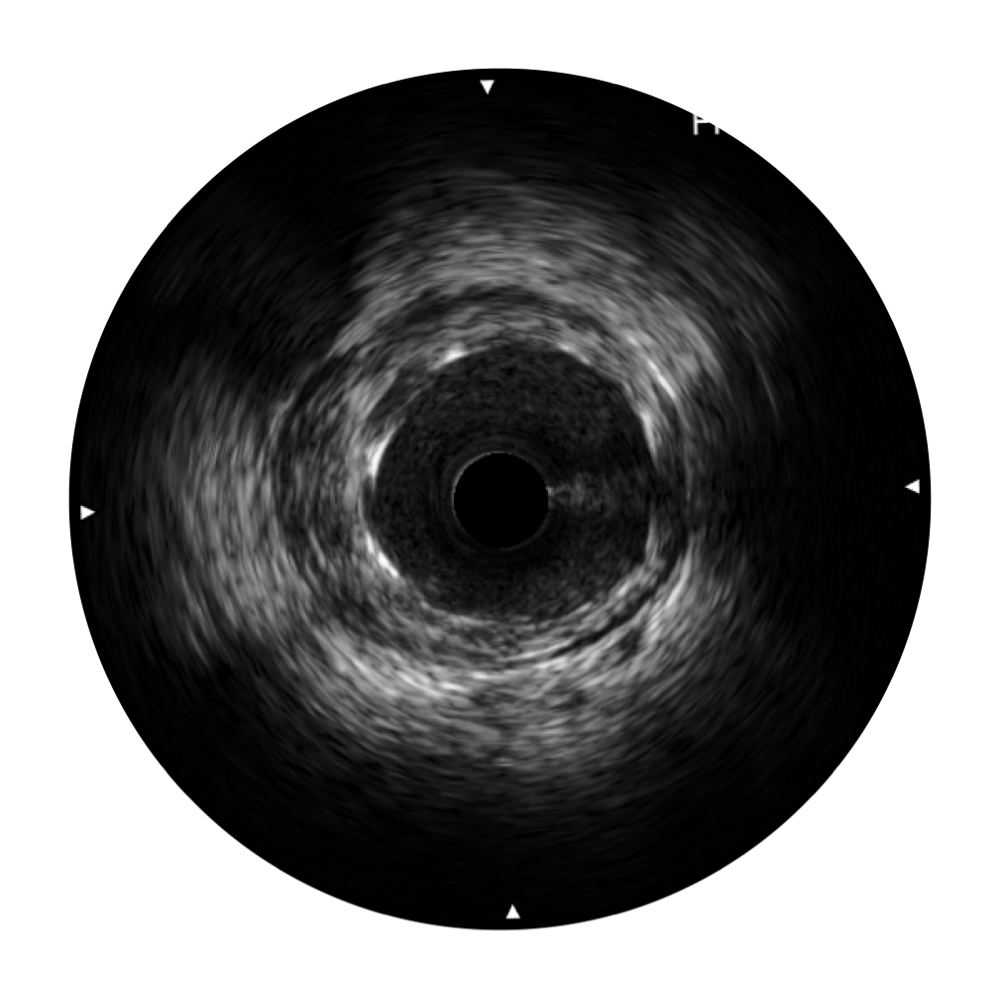

血管内超声(IVUS) 通过对病变程度、性质和累及范围的精确判断,可帮助选择治疗策略和方法,指导介入治疗过程,能够降低主要不良心血管事件,改善预后,在复杂病变介入治疗中用于指导支架置入的优势更为明显。血管内超声(IVUS)已成为精准心血管介入治疗的“金标准”。

球速体育入口超宽频成像技术覆盖20-80MHz1或20-90MHz2频率范围, 提供优异的分辨力同时也保证充足的穿透深度

对比传统IVUS导管成像,球速体育入口宽频IVUS图像的近场支架梁显影更细腻,远场中膜外血管仍清晰可辨,兼顾远中近,兼顾分辨力与穿透深度